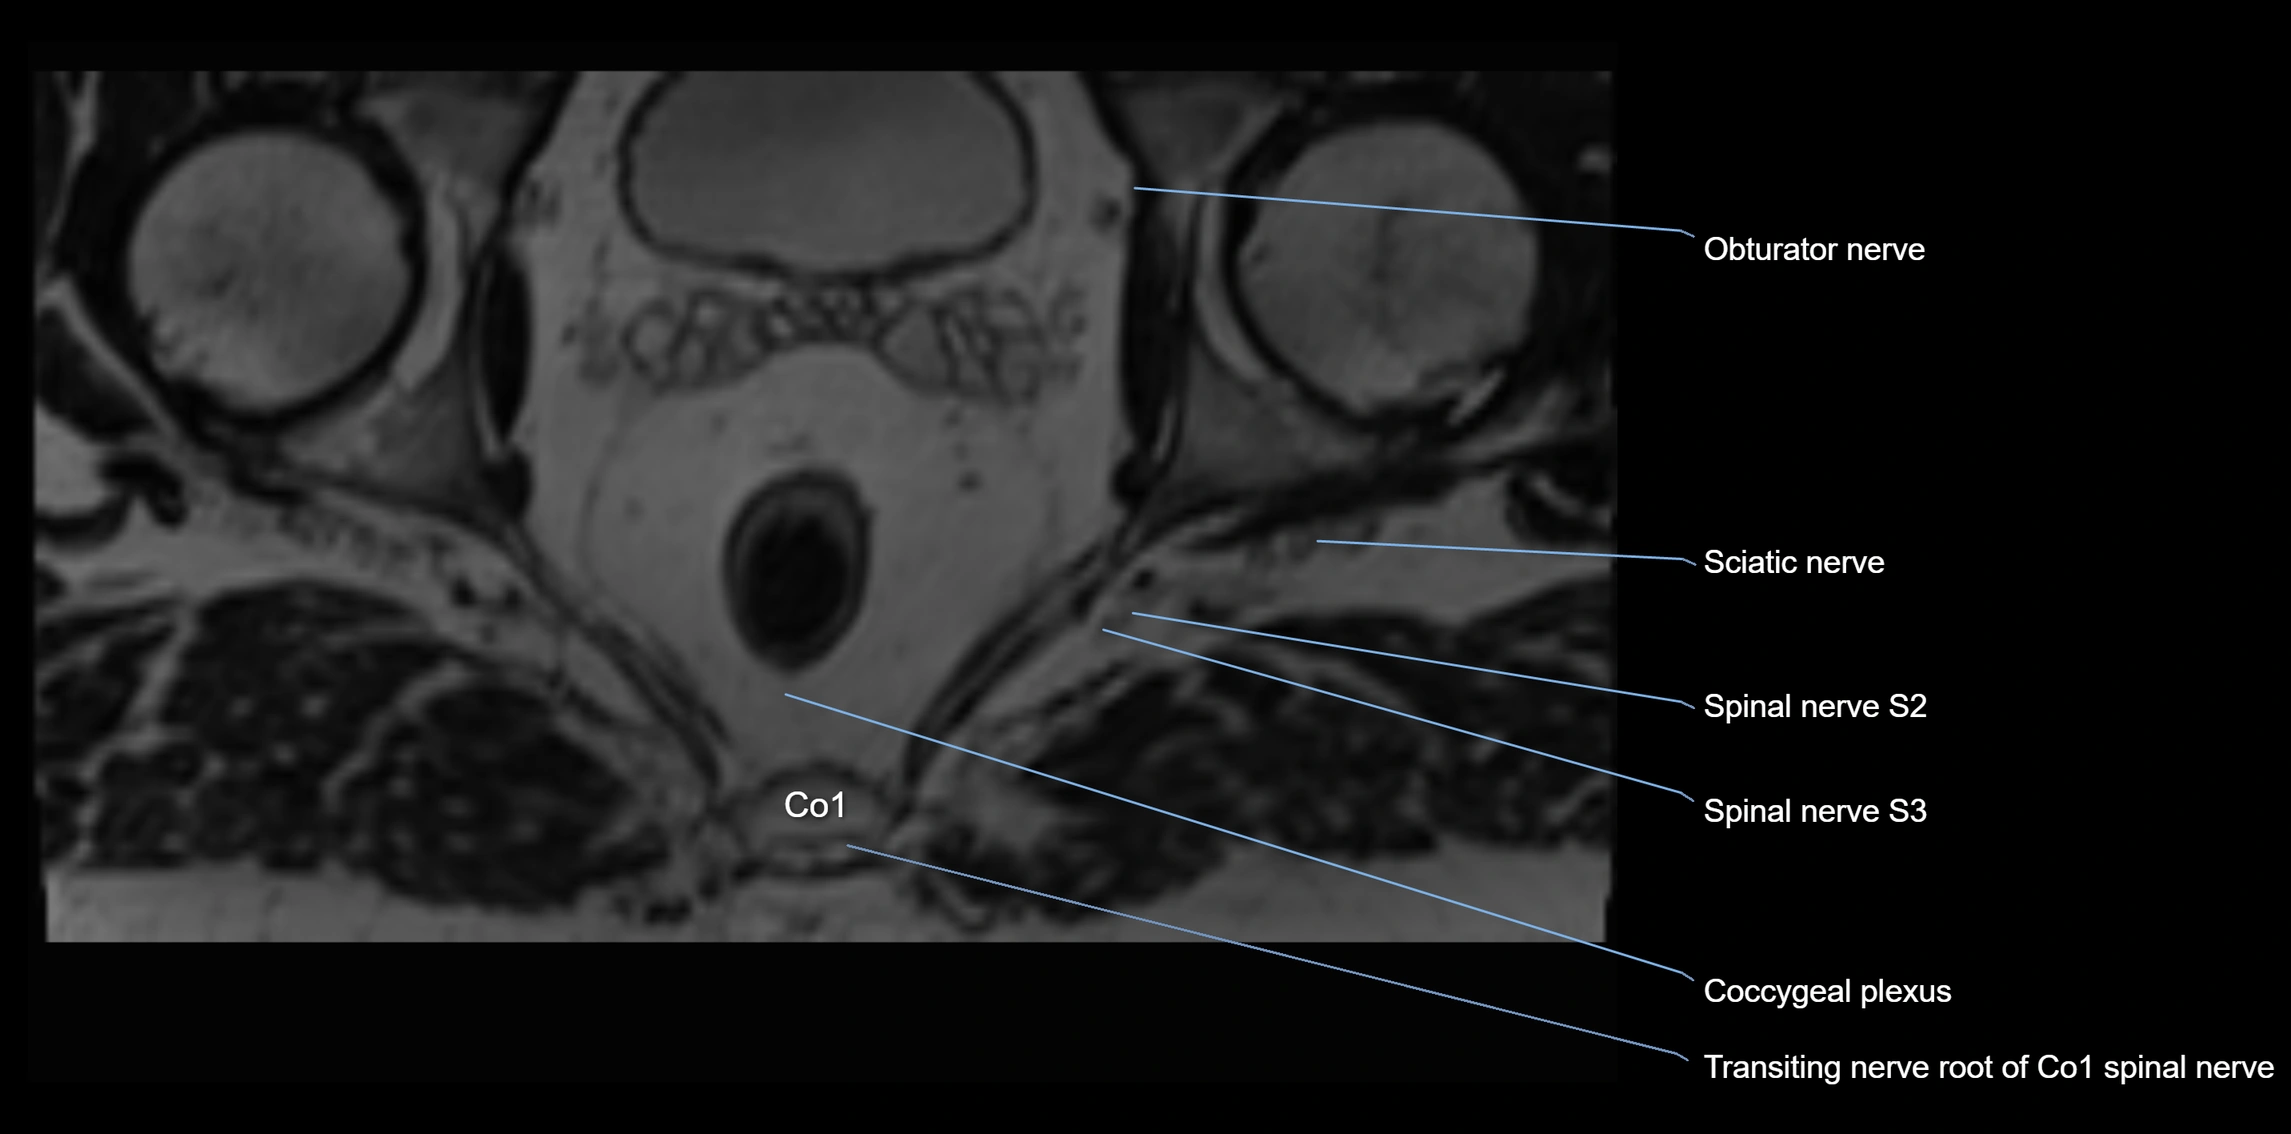

MRI image

image